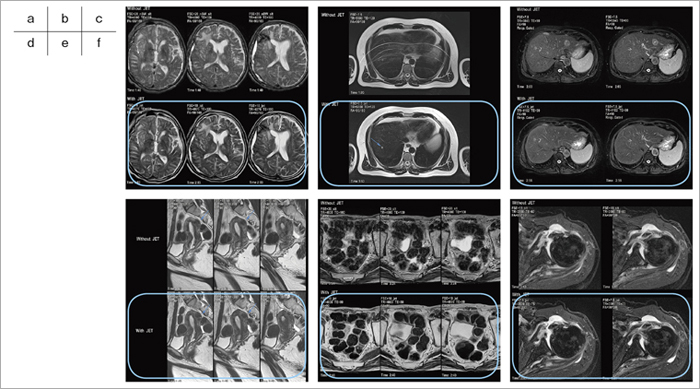

図8 各領域におけるJETと従来法の画像比較(枠内がJET法)

a:頭部でのT2強調像。動きによる影響を低減している。

b:上腹部でのT2強調像。呼吸の影響を低減している。

c:上腹部での脂肪抑制と呼吸同期併用T2強調像。体動補正と良好な脂肪抑制効果が見られる。

d:女性骨盤領域での矢状断面T2強調像。不随意運動の体動補正効果が見られる。

e:骨盤領域でのT2強調像。腸管の蠕動運動の影響を低減している。

f:肩の脂肪抑制T2強調像。呼吸の影響を低減している。

(画像ご提供:共愛会戸畑共立病院放射線科・中村克己先生・他)

体動補正法JETは,FSE法で得られた収集エコーデータの束(blade)をk空間上で回転させて充填し,画像化する手法である(図7)。これまでは,呼吸や体動の影響を受けにくい技術として頭部領域を中心に使用されている。東芝は,実用性を向上させると同時に検査領域の拡大を図った。折り返し防止機能の改良,脂肪抑制パルスの適用可能,IRパルスの適用可能,および呼吸同期機能などである。例えば,画質低下を招く大きな要因であった折り返しアーチファクトを抑制する機能については,折り返し防止(No Phase Wrap)の併用を可能とすることでFOV設定の自由度が改善され,10段階で折り返し防止のサンプリングの割合を変更できるようにした。これによって,画質低下を抑え,同時に撮像時間と分解能のバランスをより細かく設定することが可能になった。また,撮像パラメータの自由度を向上させることで,T2強調像のほかFLAIR像,T1強調像も得られるようにした。

以上の機能拡充によって,整形,腹部,骨盤部など,領域を選ぶことなく高精度かつ確実なルーチン検査が可能になった(図8)。